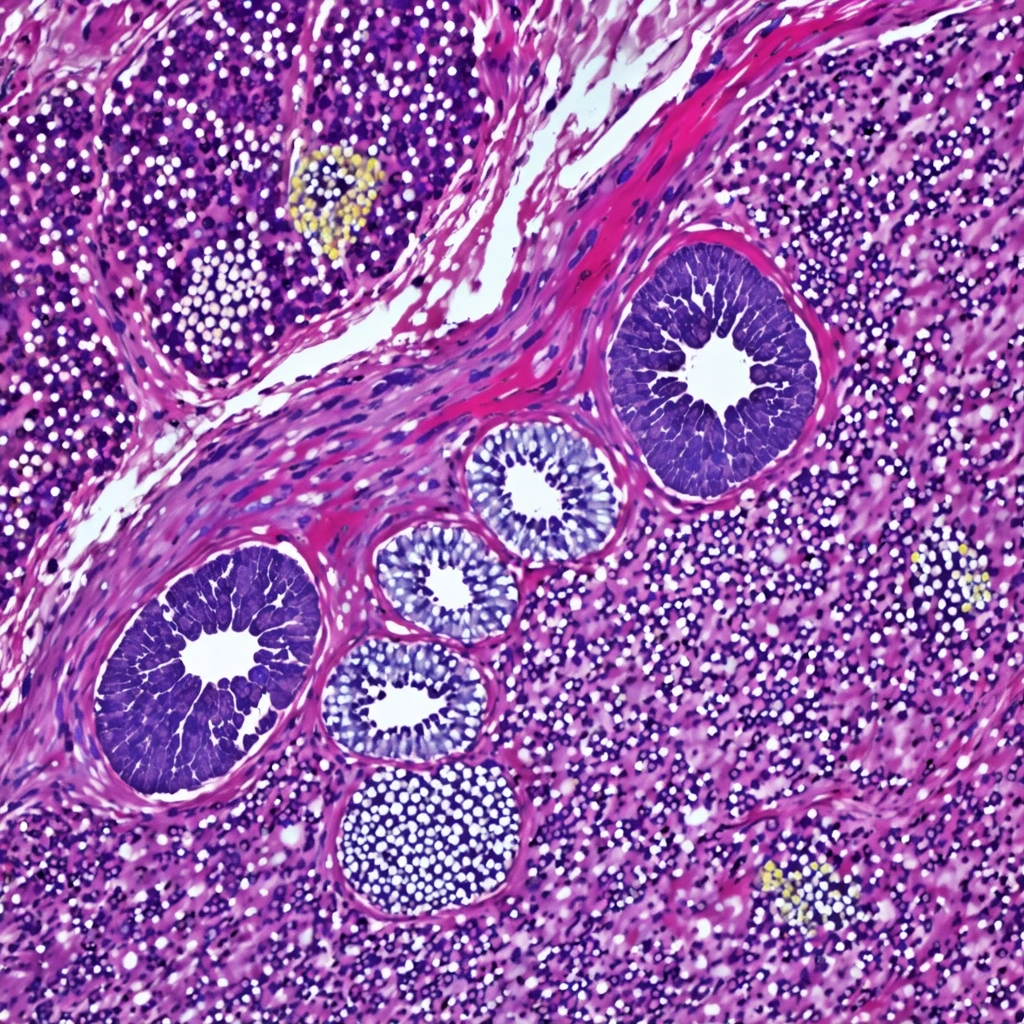

Portrai, Inc. has announced a strategic pivot to enhance the accuracy of AI-powered tumor analysis through high-resolution validation studies, addressing concerns about potential inaccuracies stemming from segmentation bleed. As breast cancer remains a critical focus, recent research emphasizes the need for reliable validation methods to distinguish true biological changes from AI artifacts, particularly in the context of aging breast tissue. This comes alongside broader advancements in CAR-T therapy aimed at solid tumors and the integration of advanced imaging techniques and proteomics, which are crucial for effective cancer treatment strategies. The ongoing commitment to rigorous validation is seen as essential for ensuring the reliability of computational frameworks in oncology drug development and patient outcomes.